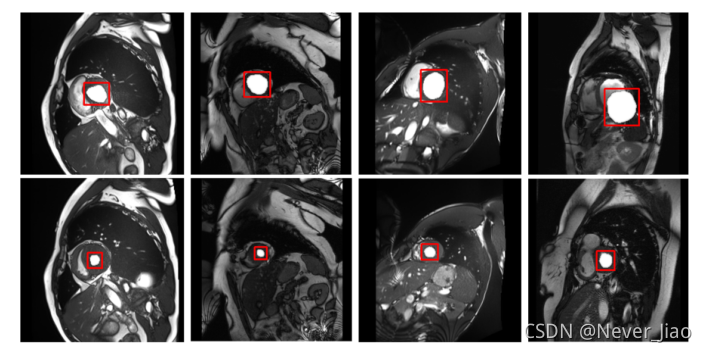

本文使用MICCAI Challage 2017[23]中的整个数据库作为我们的第一个数据集(总共来自100个主题的1922个切片),图1显示了数据集中的原始图像。正如导言中所描述的,在心脏周期的不同阶段,左心室腔的形状和大小各不相同。心脏MRI图像中存在固有的噪声和伪影。

由于在心动周期的不同阶段,不同检测器的左心室大小和整个切片的比例不同(图1),我们需要在不同的尺度上检测目标器官的特征;因此,在网络模型中通常使用多尺度推理。在编码阶段,基于不同大小的接受域范围进行多尺度特征融合,以获得高分辨率、语义丰富的特征地图。

我们在ACDC 2017数据集[23]上进行了测试,分割结果如图8所示。在这张图中,我们将MMNet的预测图与UNET模型的预测图进行了比较。对于5个病理亚组的Dice系数评估,舒张末期(ED)和收缩末期(ES)心脏的Dice系数均在90%以上,其中ED和ES的平均Dice系数分别为96.2%和93.9%。舒张末期(ED)和收缩末期(ES)的Jaccard指数分别为0.926和0.868,平均Hausdorff距离为7.0.。我们还在MICCAI2009数据集[24]上进行了测试,分割结果如图9所示。4个病理亚组的平均Dice系数为98.0%,4个病理亚组的平均Jaccard指数为96.4%,4个病理亚组的平均Hausdorff距离为5.2。在MICCAI 2018数据集[35]上,测试骰子因子为96.8%,Jaccard指数为93.7%,Hausdorff距离为7.5。实验结果表明,该模型具有较高的分割精度和稳定的分割结果。

如图8所示,两个UNET模型预测图显示孤立的假阳性器官;UNET判断腹腔中的其他明亮区域为左心室腔,而两个MMNet图都没有显示孤立的分割错误。对于HCM测试受试者,由于收缩末期乳头肌的干扰,左心室腔内有明显的不同亮度区域。分割结果表明,脑室边缘的形状与地面真实情况相符,腔内没有孤立的分割误差。NOR检测器分割结果对比度低,心内膜和心外膜边缘的信息模糊。UNET分割输出与地面真实存在形状差异;然而,我们的分割方法产生了更平滑的边缘。RV探测器切片中存在噪声和运动伪影,插图中舒张末期和收缩末期心室轮廓有显著差异,MMNet仍可进行准确分割。分割效果图表明,该方法成功地区分了心室和背景区域,即使在复杂的脑室中也是如此。